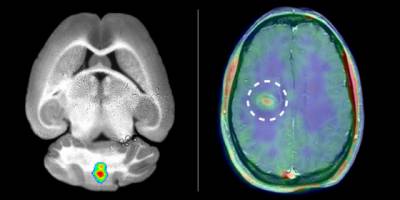

Auf Patienten übertragen, was man zuvor in der tierexperimentellen Untersuchung festgestellt hat - das ist das grosse Ziel vieler in der Biomedizin arbeitender Wissenschaftler. Gelungen ist es Forschern des Exzellenzclusters "Cells in Motion" (CiM) der Universität Münster: Sie konnten erstmals akute Entzündungen im Gehirn bei Patienten mit Multipler Sklerose (MS) bildgebend nachweisen.